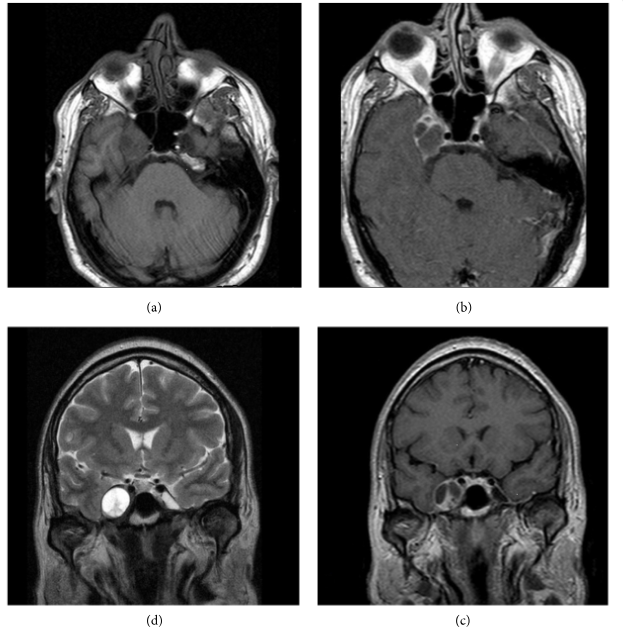

三叉神经鞘瘤是比较常见的非前庭神经鞘瘤,占颅内神经鞘瘤的1 ~ 8%,占颅内肿瘤的0.1 ~ 0.5%。常常发生在中年人身上,也可以发生在任何年龄,包括儿童。...

神经鞘瘤是起源于神经鞘的雪旺细胞的良性肿瘤。它们可以起源于任何外周神经、颅神经或自主神经。三叉神经鞘瘤少见,占全部颅内肿瘤的0.07-0.3%,占颅...